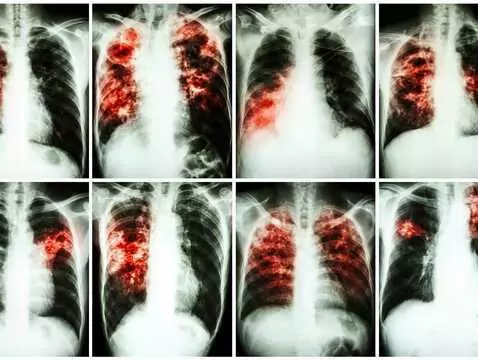

La tuberculosis: una enfermedad que no ha desaparecido. En el Día Mundial de la Tuberculosis, merece la pena recordar la información más importante sobre la enfermedad.

Hay enfermedades de las que se dice que están "extintas" o que sólo aparecen en los llamados países del Tercer Mundo. Una de esas enfermedades era la tuberculosis, considerada una entidad patológica...